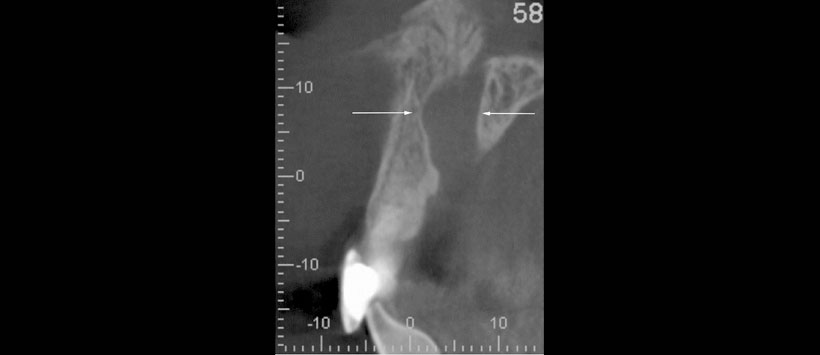

Los resultados mostraron que en el grupo de trauma (n = 96), el 31,3% tenía al menos un incisivo maxilar perdido y el 95,8% tenía incisivos con tratamiento de endodoncia. La dimensión anteroposterior del foramen incisivo (p = 0.02) y del CNP a mitad de camino (p = 0.04) fue significativamente mayor en el grupo de trauma. Significativamente se evidenció más casos con un signo abultado en el grupo de trauma (n = 19) que en el grupo control (n =3, p = 0,001). Se identificó una osteólisis apical en el 5,1% de incisivos, y 12/38 mostraron una fusión con el CNP.

El estudio concluyó que dimensiones más amplias del CNP y un signo abultado puede sugerir una lesión dentoalveolar anterior en el maxilar anterior. La osteólisis periapical del incisivo central de más de 5 mm de diámetro tiende a fusionarse con el CNP.

- Figura 3: Imagen representativa de CBCT (Accuitomo 170, campo de visión de 6 × 6 cm, tamaño de vóxel 0,125 mm) en el plano sagital que ilustra un canal nasopalatino con un agrandamiento notable, identificado como signo abultado (flechas)